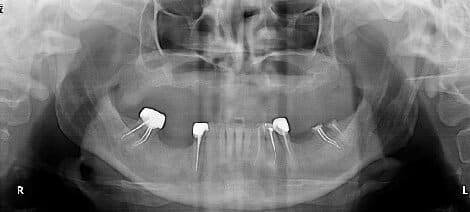

la suite du cas de 90

pour32/42 ce sont des D2 et non pas des P pano "photographies" de mauvaise qualité

à l'époque tous ça c'etait sans scanner, et c'est vrai que les axes sont...bizarre (c'est le patient qui etait tordu sans doutes

Un nouveau cas à étudier, merci du cadeau Béotien

Des avis?

sur un opt , c'est pas top pour voir quoi faire.

un ptit scan ?